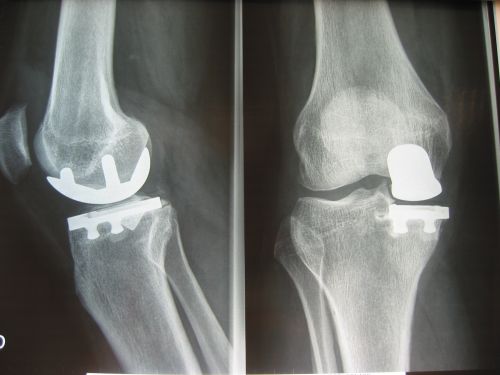

Chirurgie du genou

Prothèses totales ou partielles - nombre de poses en 2018 : 200...